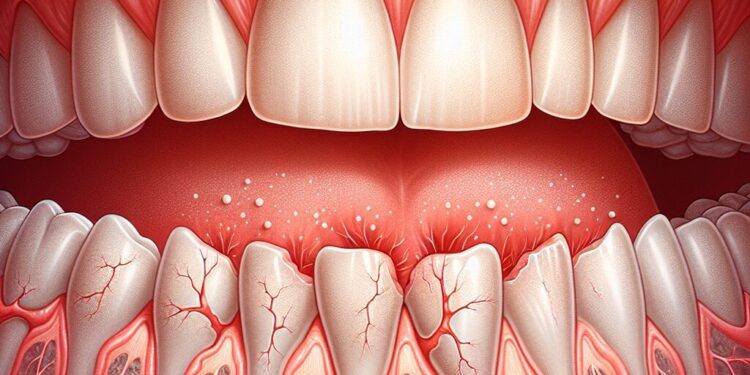

A recessão gengival é um problema comum que afeta muitas pessoas, caracterizado pelo deslocamento da margem gengival em direção à raiz do dente, expondo-a parcialmente ou completamente. Essa condição pode levar a desconforto, sensibilidade dentária e um impacto negativo na estética do sorriso, além de aumentar o risco de cáries radiculares e doenças periodontais. Compreender as causas, os sintomas, as consequências e as opções de tratamento para a recessão gengival é fundamental para promover a saúde bucal e prevenir complicações.

A recessão gengival refere-se ao desgaste ou retração da margem gengival, que é a faixa de tecido que circunda e protege os dentes. Quando essa margem se desloca para baixo, em direção à raiz do dente, parte da raíz fica exposta. Essa exposição torna a superfície radicular vulnerável a fatores externos, podendo causar sensibilidade ao calor, frio, doces e até ao toque. Além do desconforto, a recessão pode comprometer a estrutura e a estética dos dentes, aumentando o risco de problemas mais sérios.

A recessão gengival pode se manifestar de diferentes formas, e nem sempre o paciente percebe o problema imediatamente. Os principais sintomas incluem:

- Aparência de dentes “mais alongados” devido à exposição da raiz.

- Sensibilidade dentária, especialmente ao consumo de alimentos ou bebidas frias, quentes ou ácidas.

- Mudança na coloração do dente, já que a superfície radicular é mais escura que o esmalte.

- Presença de pequenas fissuras ou sulcos na margem gengival.